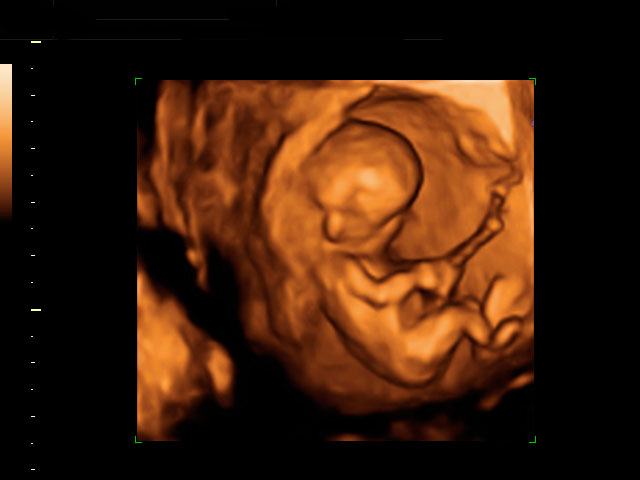

En la ecografía de la semana 12 de embarazo se distingue los genitales del feto, lo que permite saber con bastante probabilidad de acierto si se trata de una niña o un niño, como en este caso.

Cómo se ven los genitales de un feto varón de 12 semanas en la ecografía

Vemos en esta ecografía en dos dimensiones de un feto de 12 semanas. Si nos fijamos en la flecha, el tubérculo genital apunta hacia delante, lo que hace muy probable que el feto sea de sexo varón.